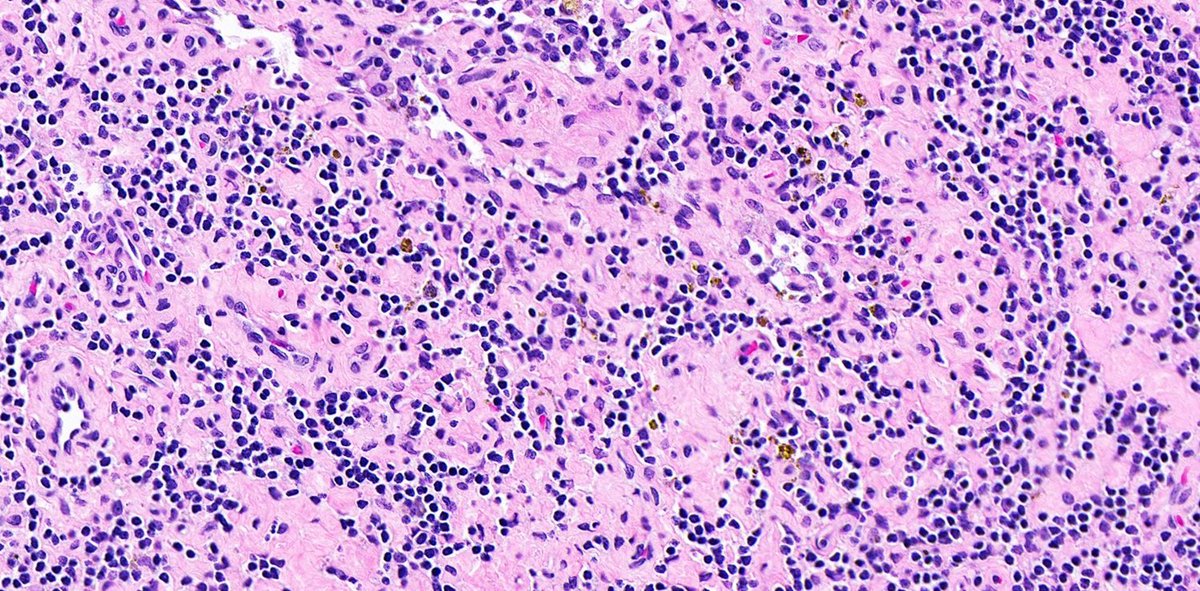

Vascular transformation of sinuses, also called nodal angiomatosis: Usually found incidentally after resection of a nearby tumor, due to obstruction of lymphatic efferent vessels or venous obstruction #Hemepath #PathX #Surgpath #PathTwitter #MedEd

Composed of a complex network of anastomosing blood vessels of variable sizes with fibrosis, irregularly branching vascular slits with extravasated red blood cells and interstitial hemosiderin deposition #Hemepath #PathX #Surgpath #PathTwitter #MedEd